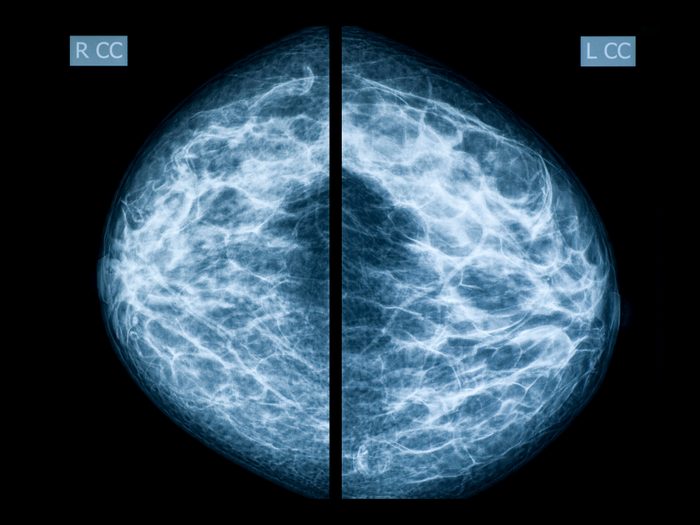

Is my breast tissue dense?

Some women—particularly younger women who are still menstruating—have more dense breast tissue, while other women (most often those who are postmenopausal) have fattier breast tissue. As women reach menopause and no longer produce estrogen from their ovaries, dense breast tissue is replaced by fattier tissue, which makes mammograms in older women easier to read.

Denser breast tissue is made up of the milk glands, milk ducts, and fibrous tissue and appears as white areas on a mammogram, says Dr. Jokich. However, most cancers also appear as white areas on a mammogram, sometimes making it difficult for radiologists to determine what is dense breast tissue and what is cancer.

“If you put a white lump or a white nodule in the middle of a dense breast that’s all white on a mammogram, you can’t see it,” says Dr. Jokich. “Dense breasts are also a risk factor for developing breast cancer.” He says women need to be aware of whether or not they have dense breast tissue and ask their doctor whether additional modalities, such as ultrasound, MRI, or molecular breast imaging, should be used to screen for breast cancer.

Currently, 38 states have passed legislation mandating that women who have dense breasts be made aware of their breasts’ density after their mammogram and that they should consult with their physician about how to screen for breast cancer. Breast density is unrelated to your breasts’ size or how they feel, so can you can have dense breasts whether your breasts are larger or smaller or feel firm or soft.